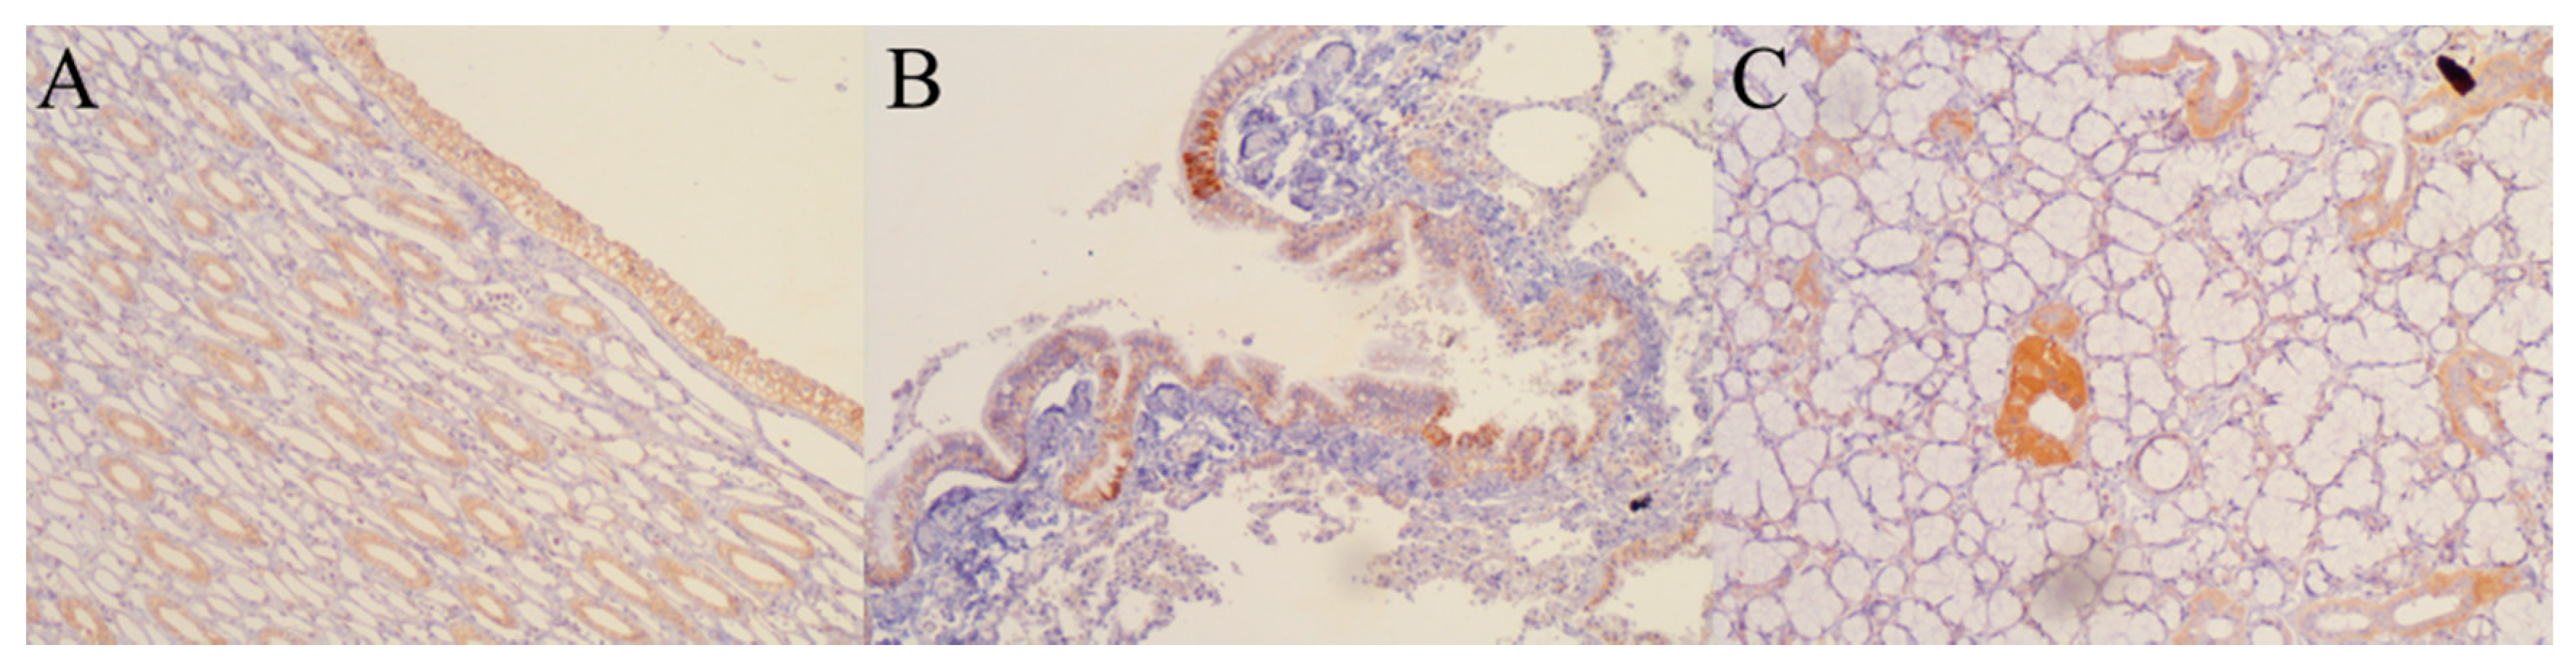

3.4. Early Biodistribution Is Not Widespread

| Tissue | RT-PCR | IHC | Tissue | RT-PCR | IHC |

|---|---|---|---|---|---|

| Kidney | + | + | Pancreas | − | − |

| Salivary gland | + | + | Adipose tissue | − | − |

| Stomach | + | − | Colon | − | − |

| Lung | − | + | Brain | − | − |

| Cancerous tissues | − | − | Cerebelum | − | − |

| Striated skeletal muscle | − | − | Adrenal gland | − | − |

| Fibroadipose tissue | − | − | Cell package | − | − |

| Nervous package | − | − | Serum | − | − |

| Liver | − | − | Cerebrospinal fluid | − | − |

| Squamous mucosa | − | − |